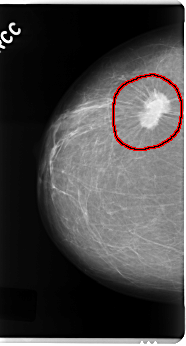

FILE: C_0121_1.RIGHT_CC.OVERLAY

TOTAL_ABNORMALITIES 1

ABNORMALITY 1

LESION_TYPE MASS SHAPE IRREGULAR MARGINS SPICULATED

ASSESSMENT 5

SUBTLETY 5

PATHOLOGY MALIGNANT

TOTAL_OUTLINES 1

BOUNDARY